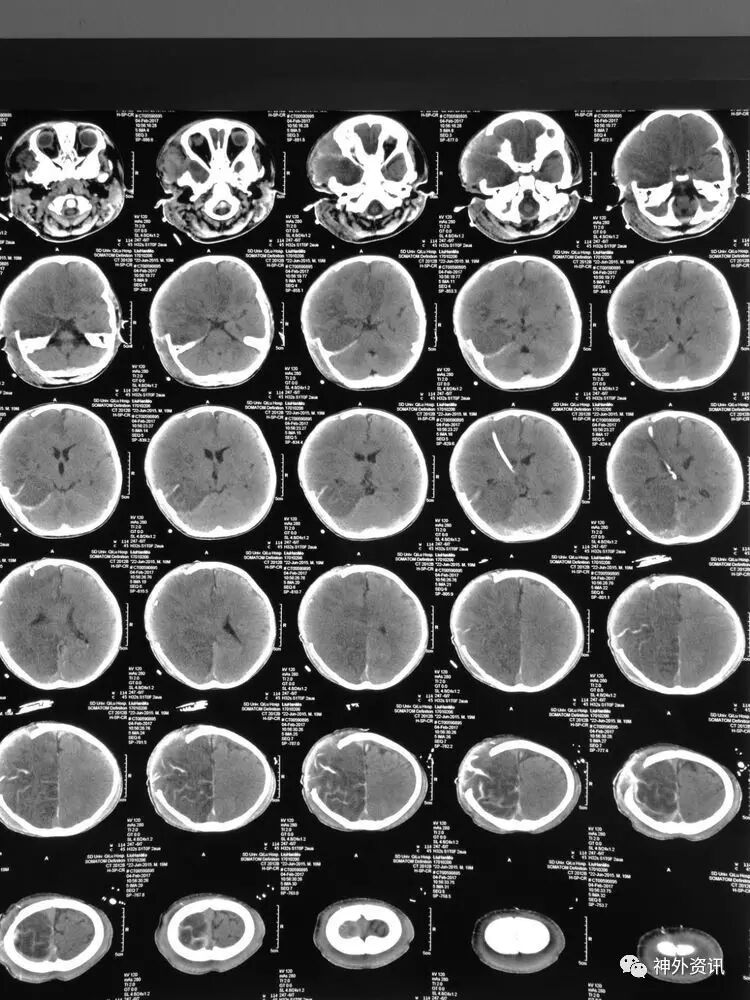

3小时后转至我院急诊科,当时查体:刺痛不睁眼,不发音,刺痛右侧肢体屈曲,右侧瞳孔5mm,对光反应消失,左侧瞳孔0.3cm,对光反应迟钝,立即术前准备并复查CT,结果示右额颞顶枕硬膜下血肿,右侧大脑半球及左侧额叶弥漫性低密度,考虑缺血,中线左移明显,脑沟及环池显示不清:

术后移动CT结果示中线移位较术前减轻,顶枕部蛛网膜下腔出血:

2017.2.1:术后2天复查颅脑CT,结果示中线居中,右侧半球低密度并SAH,左侧半球未见明显异常,左侧脑沟可见显示,双肺少量炎症,不能放松警惕,继续同前治疗。

2017.2.4:术后5天复查颅脑CT,结果示中线居中,左侧半球及环池显示清晰,右侧半球脑沟显示欠清晰,脑组织低密度较前有所好转,继续同前治疗。已加用预消化肠内营养液及促进胃肠动力药物。

2017.2.6:术后7天,复查颅脑CT示情况较前进一步好转,逐步撤掉冰毯,缓慢自然复温。

2017.2.8:术后9天,复查颅脑及胸部CT,结果显示双侧脑沟脑回及环池显示清晰。颅压控制,拔除引流管探头,头部敷料稍加压包扎,此时已更替力月西为丙泊酚,停用呼吸机。